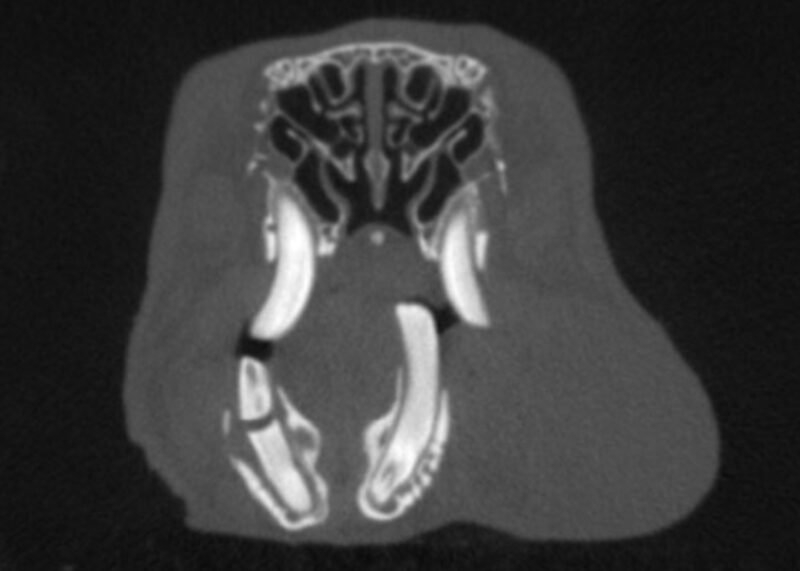

1. Im Grunde ist die Bildgebung bei Zahnerkrankungen von kleinen Heimtieren genauso wichtig wie bei Hunden und Katzen. Vor allem beim Meerschweinchen findet man die Veränderung oft erst durch Röntgen oder CT und nicht durch eine Maulhöhlenuntersuchung. Daher gehört Bildgebung zu jeder Zahnbehandlung dazu.

3. Heutzutage haben wir Zugang zu den neusten Technologien. Mit den neuen CBCT-Geräten, Flatpanel Röntgenplatten und dentalen Röntgen können wir gestochen scharfe Bilder von Kaninchen bis zu Degu-Schädeln machen. Diese Technologie hat es aber auch verdient, dass man sie richtig benutzt. D.h. die Tiere sollte perfekt gelagert werden und am besten in Sedation oder Narkose, damit man auch sehr gute Bilder bekommt.

Grundsätzlich profitieren alle Kaninchen, Meerschweinchen und Chinchillas mit Zahnerkrankungen von CT-Aufnahmen, da die Aufnahmen schnell erstellt sind und viel mehr Informationen liefern als Röntgenbilder. Vor allem bei Tieren mit Abszessbildung empfiehlt sich eine CT-Untersuchung, um Operationen, bzw. Extraktionen besser planen zu können. Idealerweise sollten diese dann auch mit Kontrastmittel durchgeführt werden. Aber auch Otitis und Rhinitis sind zwei Erkrankungen bei Kaninchen, welche idealerweise durch CT-Untersuchungen weiter abgeklärt werden.